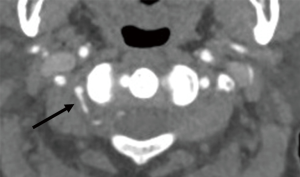

All the images were reviewed in consensus by three radiologists, each of whom had at least ten years of experience in CT diagnosis. By consulting the three-section classification criteria of V3 (13,28), we divided V3 into three subsegments: vertical portion originating from the foramen of C2, horizontal portion originating from the foramen of C1, and extradural portion originating from the posterior atlantooccipital membrane and ending at the site of piercing the dura. The three subsegments were referred to as V3v, V3h, and V3e, respectively (Figures 1-4). The number of branches was recorded. With regard to the arrangement of the branch of V3, the number 0 indicated no branches in the subsegment, and the number 1 indicated no less than one branch in the subsegment (Figure 1). There were eight kinds of arrangements of the branches altogether (000; 100; 110; 111; 010; 011; 001; 101). After an agreement was reached by consensus, all the data were confirmed. The reproducibility was assessed by comparing a subset of measurements made on 100 randomly selected cases. The radiologists were blinded to the measurements taken by the other radiologists. The 100 cases were reviewed by three observers, and interobserver agreement was calculated. All the data were imported into R statistical software, version 3.6.1, to be processed further.

The vertebral artery has a tortuous shape to meet the need for flexible movement and to facilitate smooth blood flow. V3 is anatomically defined as the vertebral artery that passes from the foramen of C1 to the site of the piercing dura, and it is radiologically defined as the artery passing from the foramen of C2 to the piercing site (26,27). Considering the occipito-atlantoaxial complex is a functional complex, we adopted the latter definition. The V3 that was identified was then divided into two portions demarcated by the foramen of the C1 process, namely, the horizontal and vertical portions, as reported in previous studies. In this study, we divided V3 into three subsegments, namely, the V3v, V3h, and V3e subsegments (13,29). V3e was the section passing from the posterior atlantooccipital membrane to the site of piercing the dura (28). The V3v was easily identified on CTA images. The starting point of V3e was defined as the point of intersection of the course of V3 and the superior border of C1 to which the posterior atlantooccipital membrane attached (29). The terminal point of V3e was marked by the density difference between the cerebrospinal fluid and dura mater on CTA images. The branch arising from V3h was defined as the suboccipital artery of Salmon that supplied the neighboring muscles. The frequency of the artery of Salmon was 20% in a study of 10 cadavers and 67% a study of 15 cadavers (26,27). The frequency of the artery of Salmon was 17.07–20.21% in V3h. Our results are consistent with those reported by Tubbs RS et al. Three branches arising from the V3h were discovered by dissecting cadavers (27), while no more than 2 branches were revealed in our research. The frequency of the branch was 25% in V3v and less than 6% in V3e. The rate of asymmetry in the arrangements of the branches of V3 was 30% according to the autopsy; in other words, the rate of symmetry was 70% in the arrangements (27). In our study, all eight arrangements of branches of V3 were symmetric, regardless of the sex and side of the patient. The permutation of (0,0,0) was the most frequently occurring permutation, followed by (1,0,0), and (0,1,1) was the least frequent (Table 3).